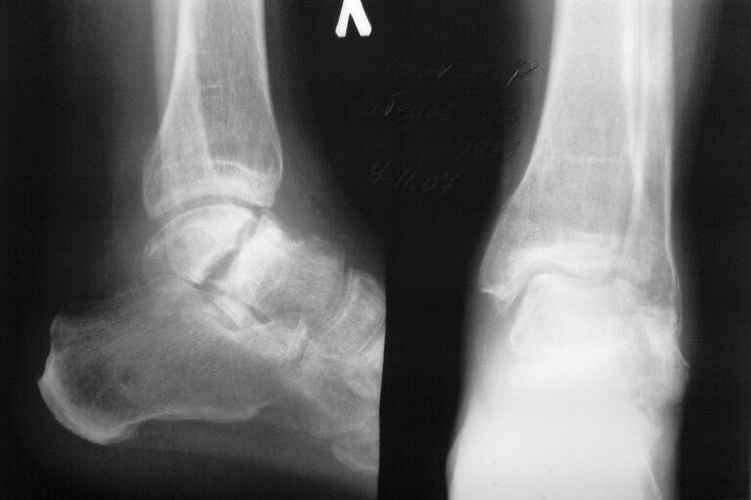

Its a grave picture.

I doubt whether 2 stages- reduction and fusion followed by a prosthesis+ subtalar fusion would be better-a pantalar fusion or talectomy would be the best-depending on soft tissue stage and vascularity of the talus and general health

Магниторезонансная томогорафия более информативна для остеонекроза тарана.

На ренгенограмме между передней и задней частями

тарана нет большой разницы костных структур,

сохранный таранный купол и имеется склероз на месте несращения. Трудно угадать дальнейший процесс, но я бы остановился на подтаранном артродезе с фиксацией перелома. Таким образом, можно сохранить опороспособность и движения в голеностопе.